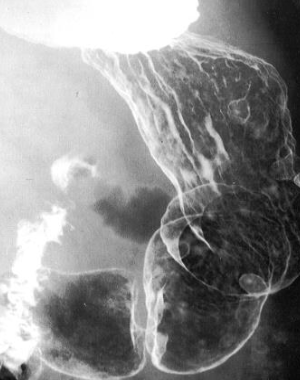

Neoplasm malign gastric ulcero-vegetant